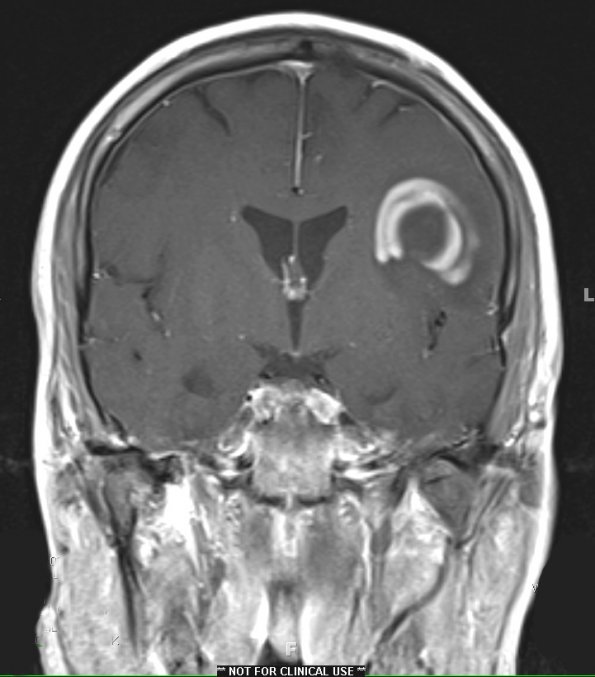

Washington University Experience | MYELIN (IMMUNE-MEDIATED) | Balo Concentric Sclerosis | 1B6 Balo Concentric Sclerosis (Case 1) MRI 8 T1 With contrast - Copy (2)

Coronal T1-weighted image with contrast demonstrates concentric rings with alternating hyperintensity and isointensity. Enhancement does not typically form continuously around the entire lesion. Incomplete ring enhancement is a pattern which is more common in demyelinative disease than high grade gliomas